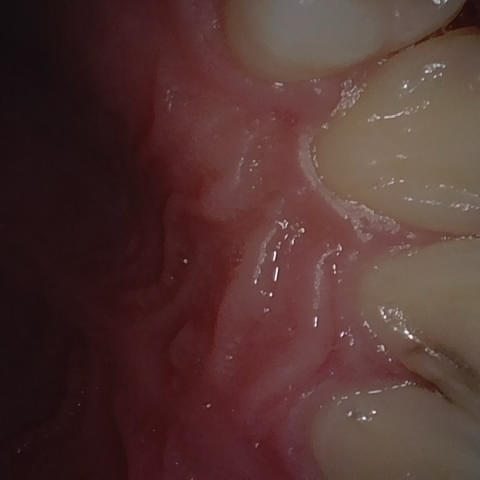

Annotated as "Good"

Original Image Rendering Image